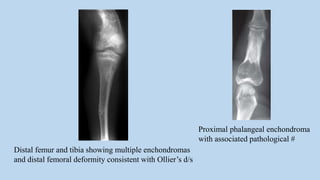

Distal femur and tibia showing multiple enchondromas

and distal femoral deformity consistent with Ollier’s d/s

Proximal phalangeal enchondroma

with associated pathological #